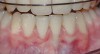

Fig 2. Pre-treatment clinical view of a 28-year-old patient with Miller Class I recession of the lower left central incisor treated with conservative SPT.

Figure 2